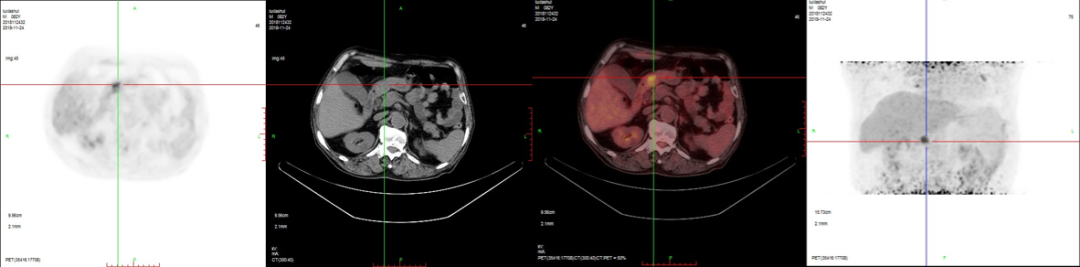

2、肝臟轉(zhuǎn)移。